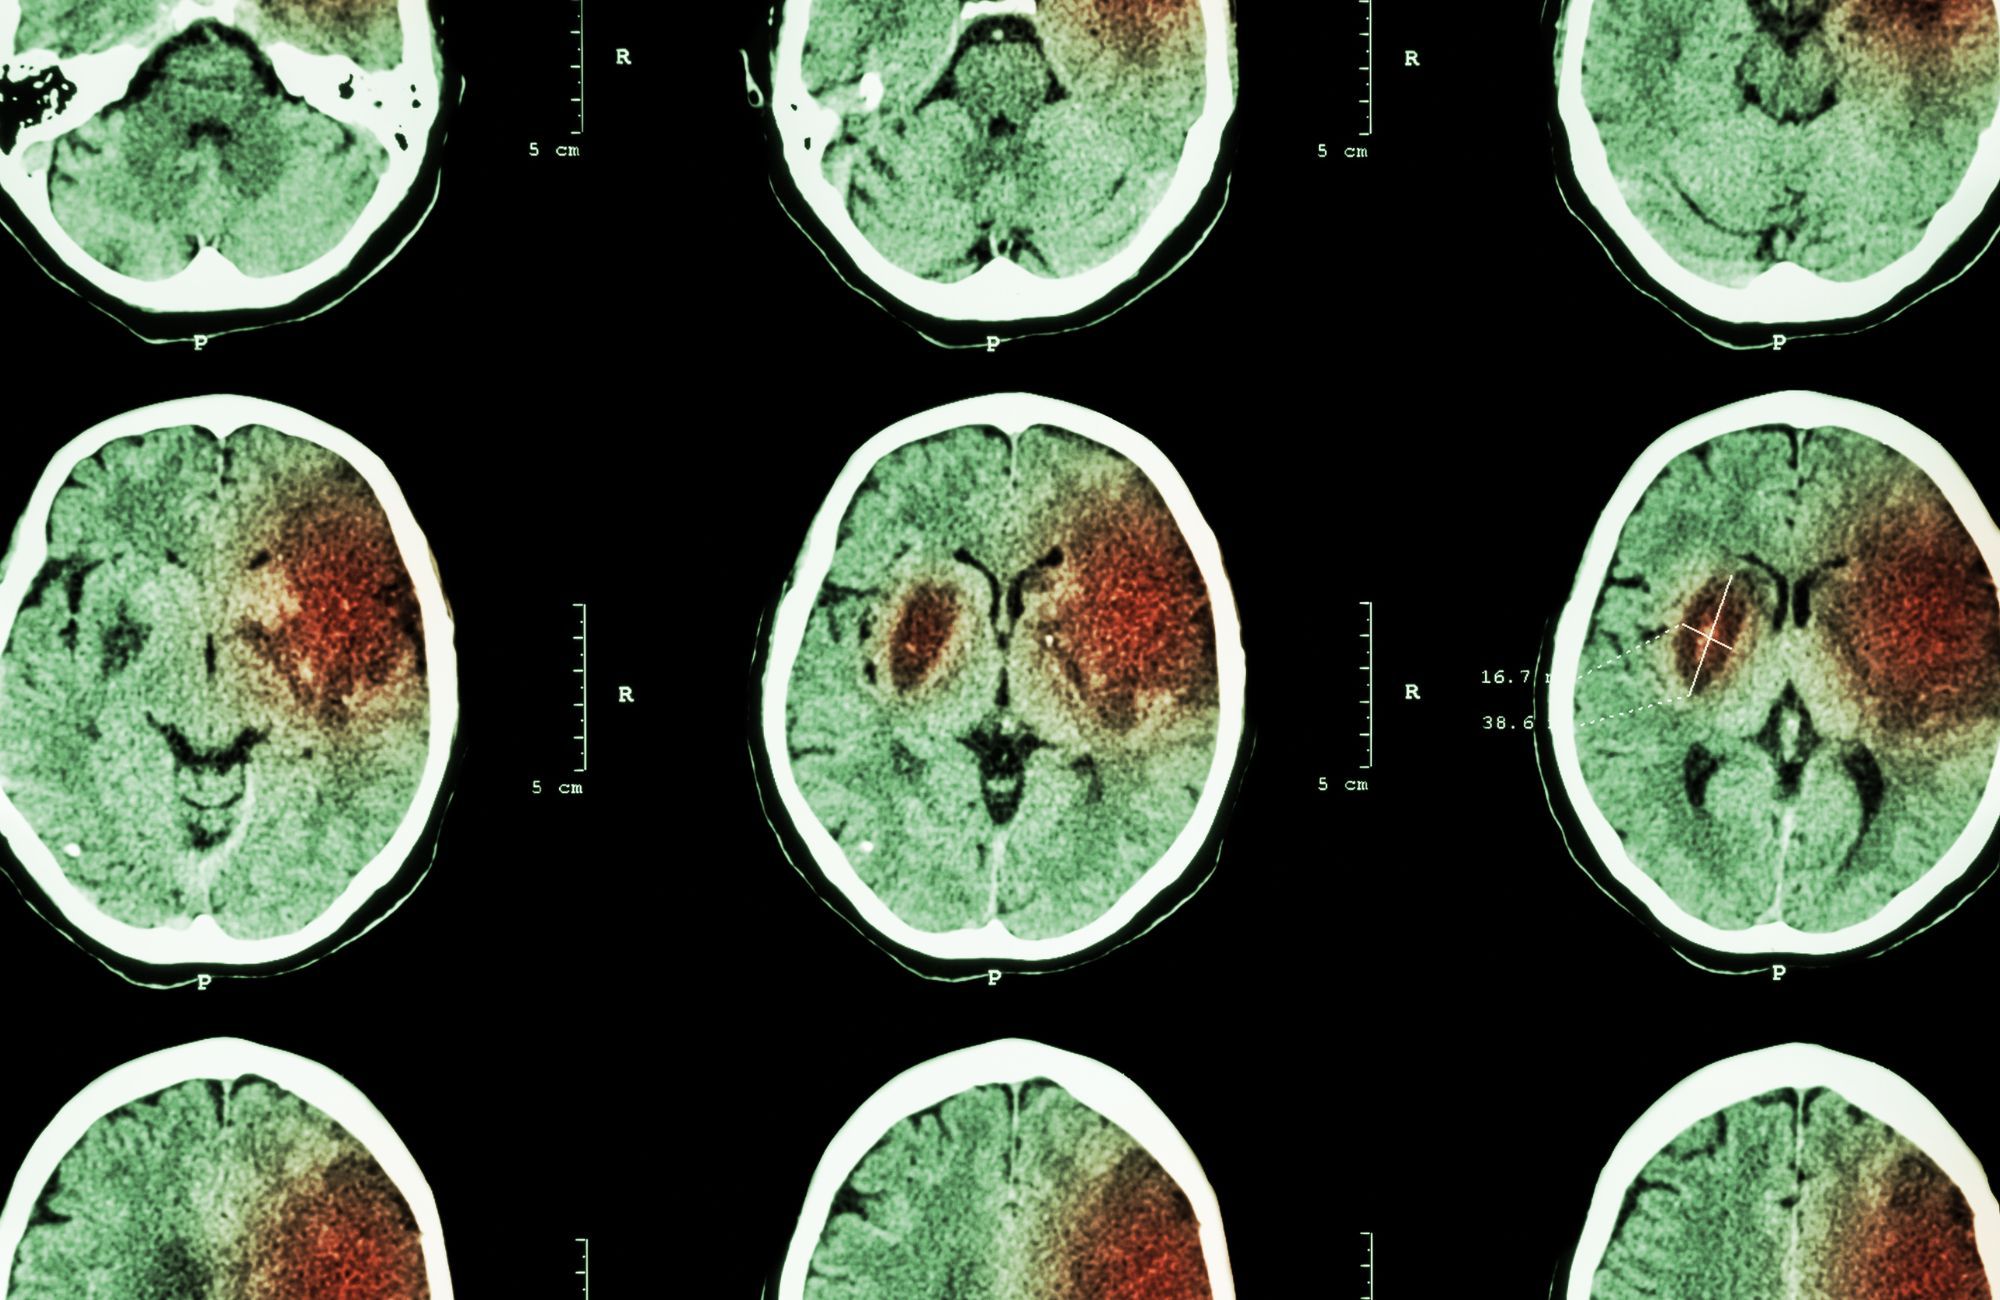

Recentemente, o cantor Sidney Magal ficou internado por cerca de dez dias depois de um acidente vascular cerebral (AVC), resultado de um quadro de hipertensão arterial. Vários estudos corroboram que a hipertensão arterial é um fator de risco importante para o desenvolvimento de um acidente vascular cerebral (AVC).

O AVC pode acometer áreas diferentes do nosso cérebro, assim como o tamanho da área acometida pode ser diferente de pessoa para pessoa. “Por isso, algumas pessoas podem ficar com sequelas e outras não. Porém, quem apresenta AVC que acomete uma área muito nobre do cérebro ou muito grande, pode ter sequelas irreversíveis e que podem afetar sua qualidade de vida. Por isso, a prevenção dessa doença é tão importante”, finaliza a cardiologista.